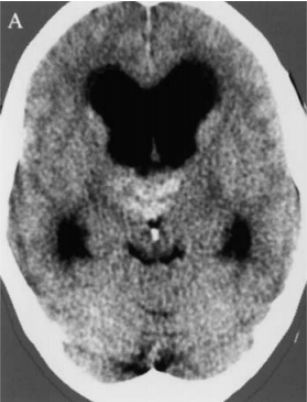

术后颅脑CT

Bella双丘脑海绵状血管瘤导致Monro双孔脑脊液阻塞、颅内压升高。由于由于脑脊液通路在Monro孔、Sylvius导水管受阻,因此需要先放置脑室-腹腔分流术治疗梗阻性脑积水。在随后的手术中,巴特朗菲教授最终通过经胼胝体入路全切病变,手术成功,无其他任何神经功能缺损。